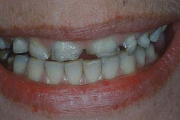

Turritavad ülemised lõikehambad.

ettepoole ulatuvad ülahambad